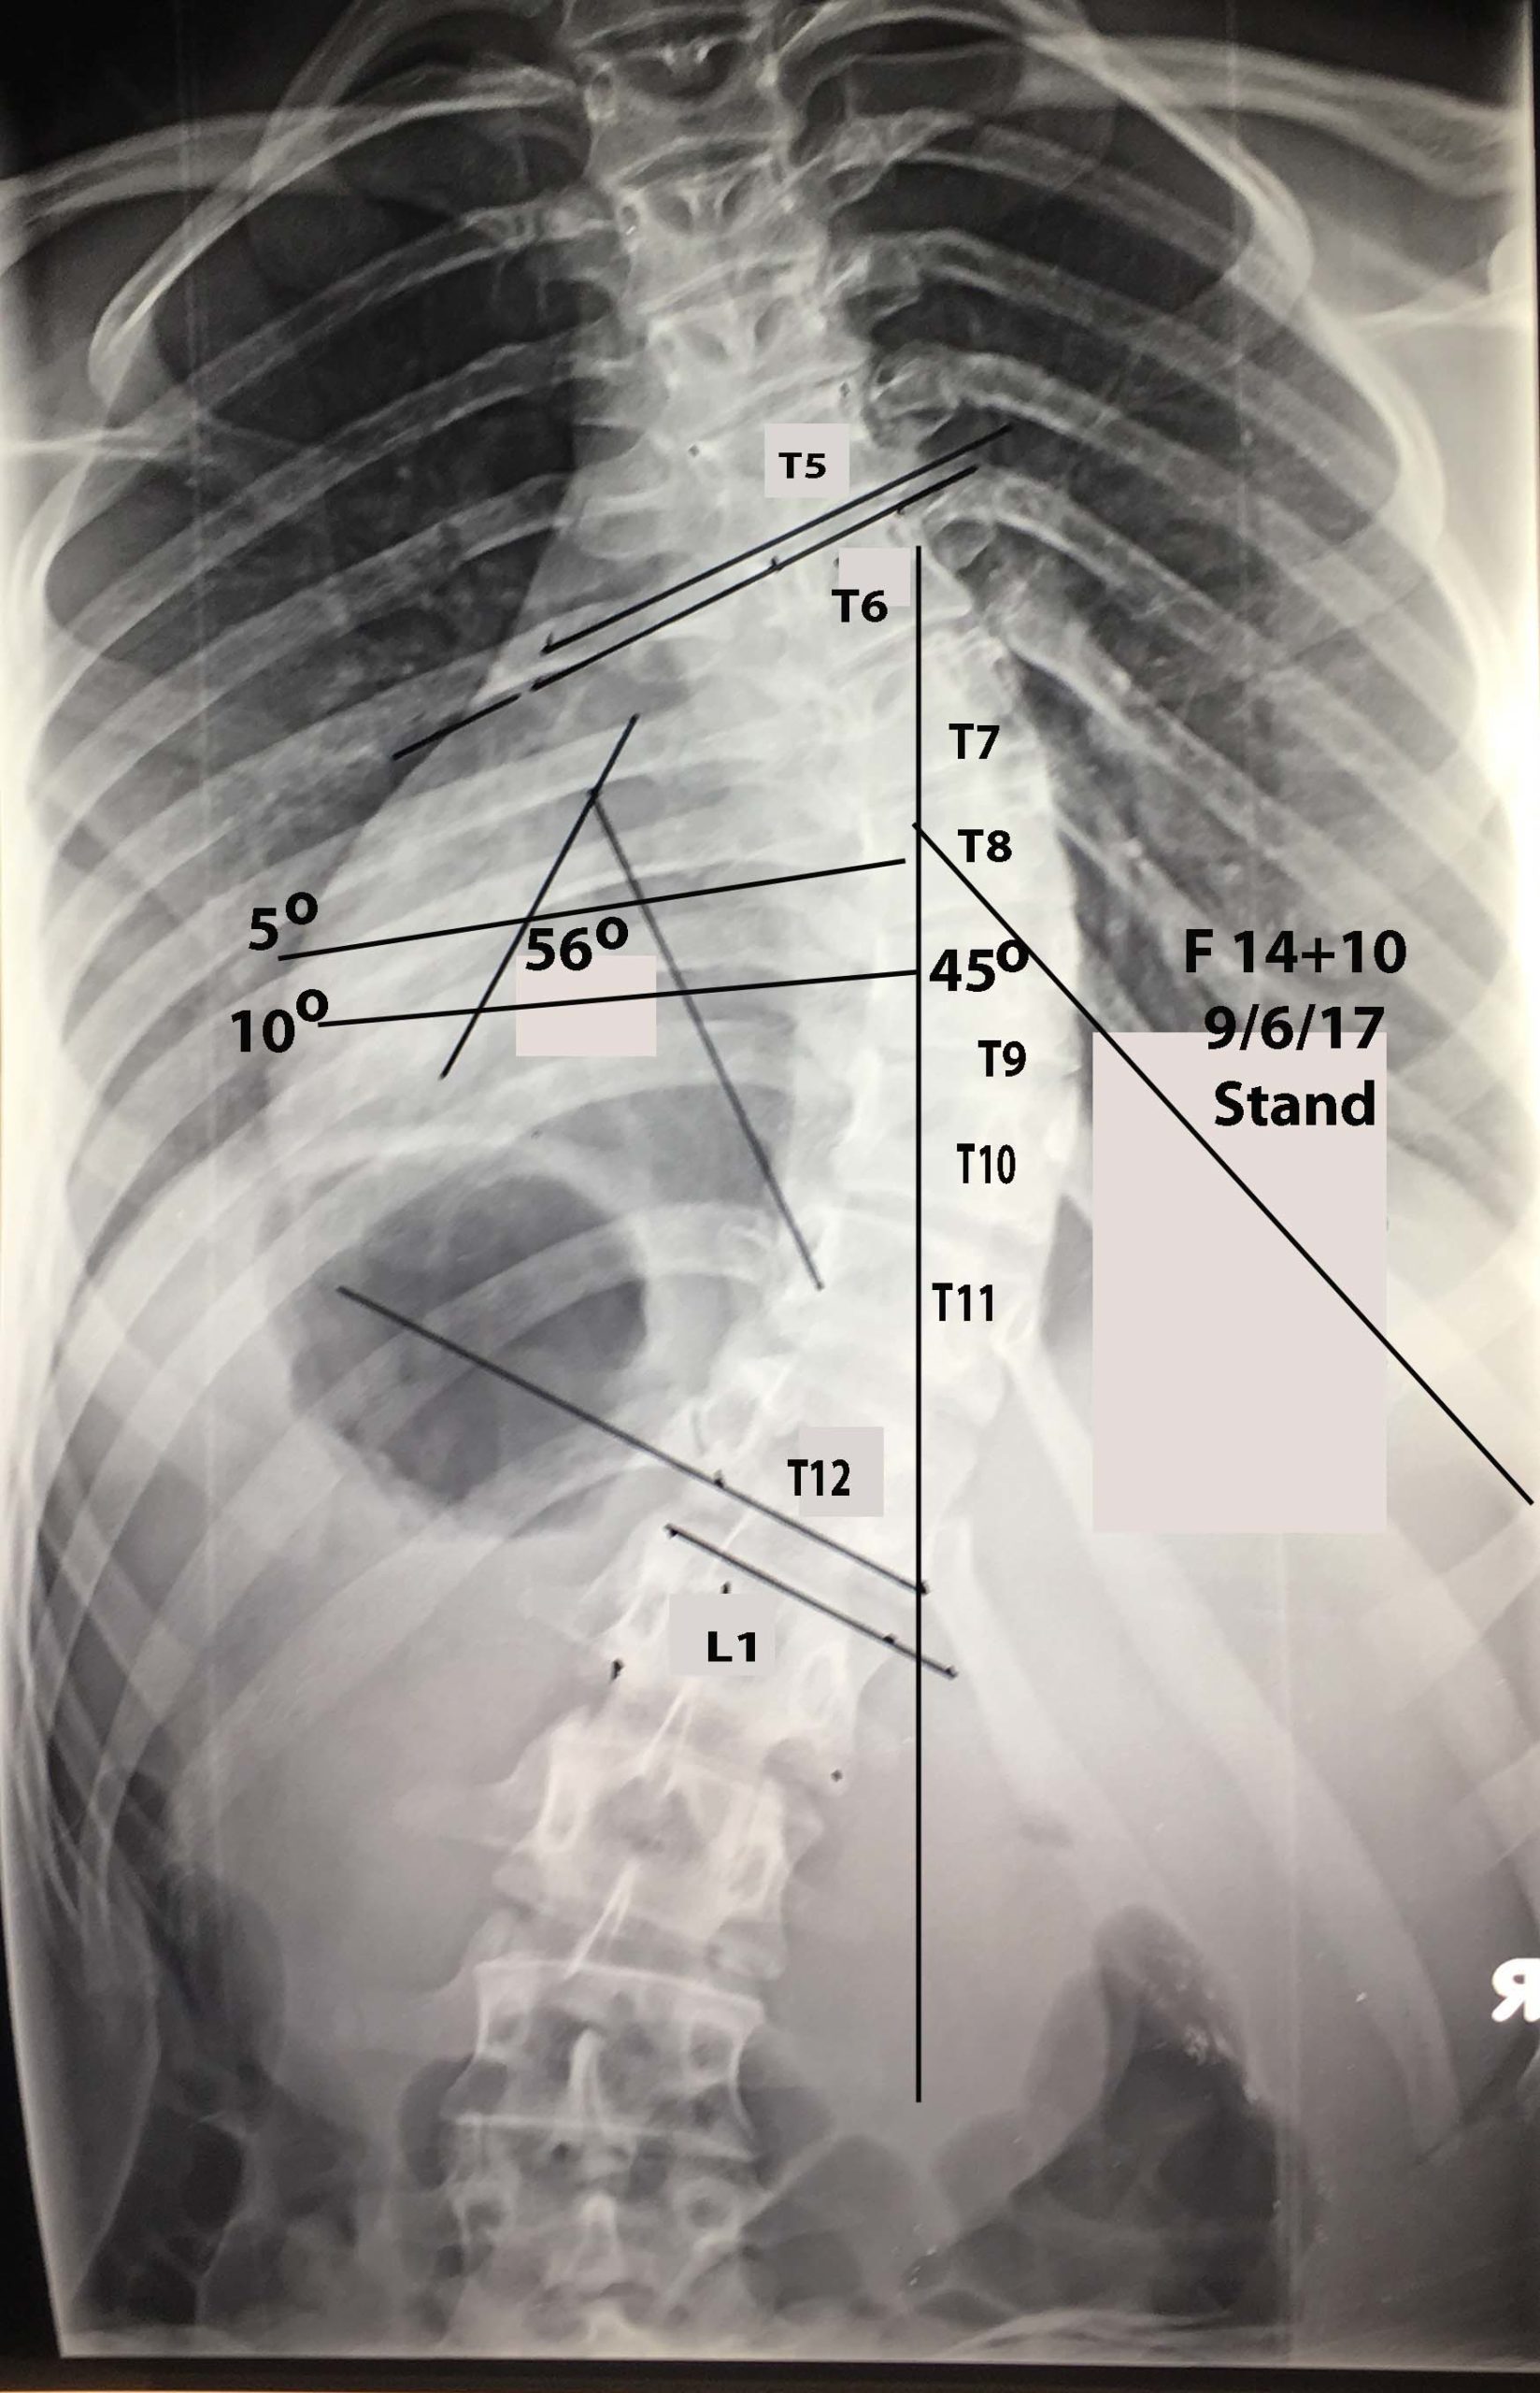

Εικόνα 3 Προσθιοπισθία ακτινογραφία Σπονδυλικής Στήλης, σε όρθια στάση

Το θωρακικό κύρτωμα είναι 56 μοίρες. Παρατηρείται μεγάλη «πτώση» των δεξιών θωρακικών πλευρών, γεγονός που αιτιολογεί το σημαντικό θωρακικό ύβο.

Η πάσχουσα, παρά το νεαρό της ηλικίας της, 14 ½ χρονών, πρακτικά είναι βιολογικά ώριμη, δεδομένου ότι έχει πραγματοποιηθεί σχεδόν πλήρως η κάλυψη της λαγονίου ακρολοφίας, από τη λαγόνιο υπόφυση (σημείο Risser 4-5).

Εικόνα 14  Προσθιοπισθία προεγχειρητική ακτινογραφία

Στο επίπεδο του κορυφαίου σπονδύλου του θωρακικού κυρτώματος (9ος) των 56 μοιρών  κατά Cobb, η πλευρά στο επίπεδο του φέρεται στο κοίλο του κυρτώματος υπό  γωνία 10 περίπου μοιρών. Ενώ στο αυτό επίπεδο δεξιά στο κυρτό μέρος του κυρτώματος, φέρεται υπό  γωνία 45 περίπου μοιρών.

Ανάλογες είναι περίπου οι πλευροσπονδυλικές γωνίες της 6ης, 7ης, 8ης, 9ης, 10ης πλευράς στο κοίλο (αριστερά) και στο κυρτό (δεξιά) του θωρακικού κυρτώματος.